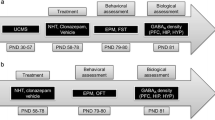

Experimental procedure

On the afternoon before an experimental day, rats were weighed and housed individually in a type III Macrolon® cage, located on a telemetric receiver. The telemetric transmitters were activated using a magnet. Data collection was subsequently started. The day after, the SIH procedure was initiated, consisting of an injection (intraperitoneal [i.p.] or oral [p.o.]) with vehicle or a certain drug dose. Immediately after injection, rats were placed back into their individual cage. Rats were placed in a novel cage (clean cage with fresh bedding and a paper tissue) 60 min later and left undisturbed for approximately 2 h afterwards. At the end of the experimental day, rats were group-housed again and transmitters were turned off. To prevent habituation to the novel cage procedure, the interval between two experiments was set to be at least 1 week. A within-subject design was used, and all animals received all (combined) doses of the drugs.